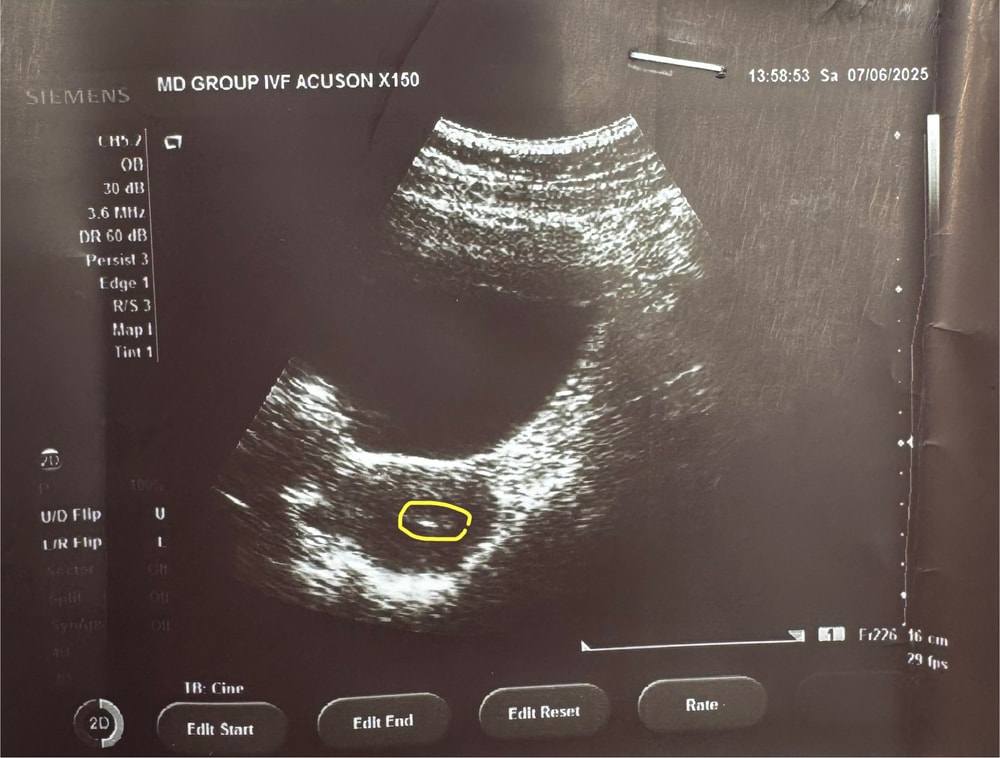

✔️ Эдик 10,5мм, Ре говорит шикарный эндик по структуре (однородный)

✔️ Прог сдавать НЕ нужно. У меня 2 желтых тела, одно из которых нереалтно бомбическое (огромное и красивое). Поддержки Утриком достаточно

Ре сказала, что у меня типа все круто. Эмбрион крутой после ПГТ, желтые тела аж 2 и одно роскошное. Эндик офигенный.